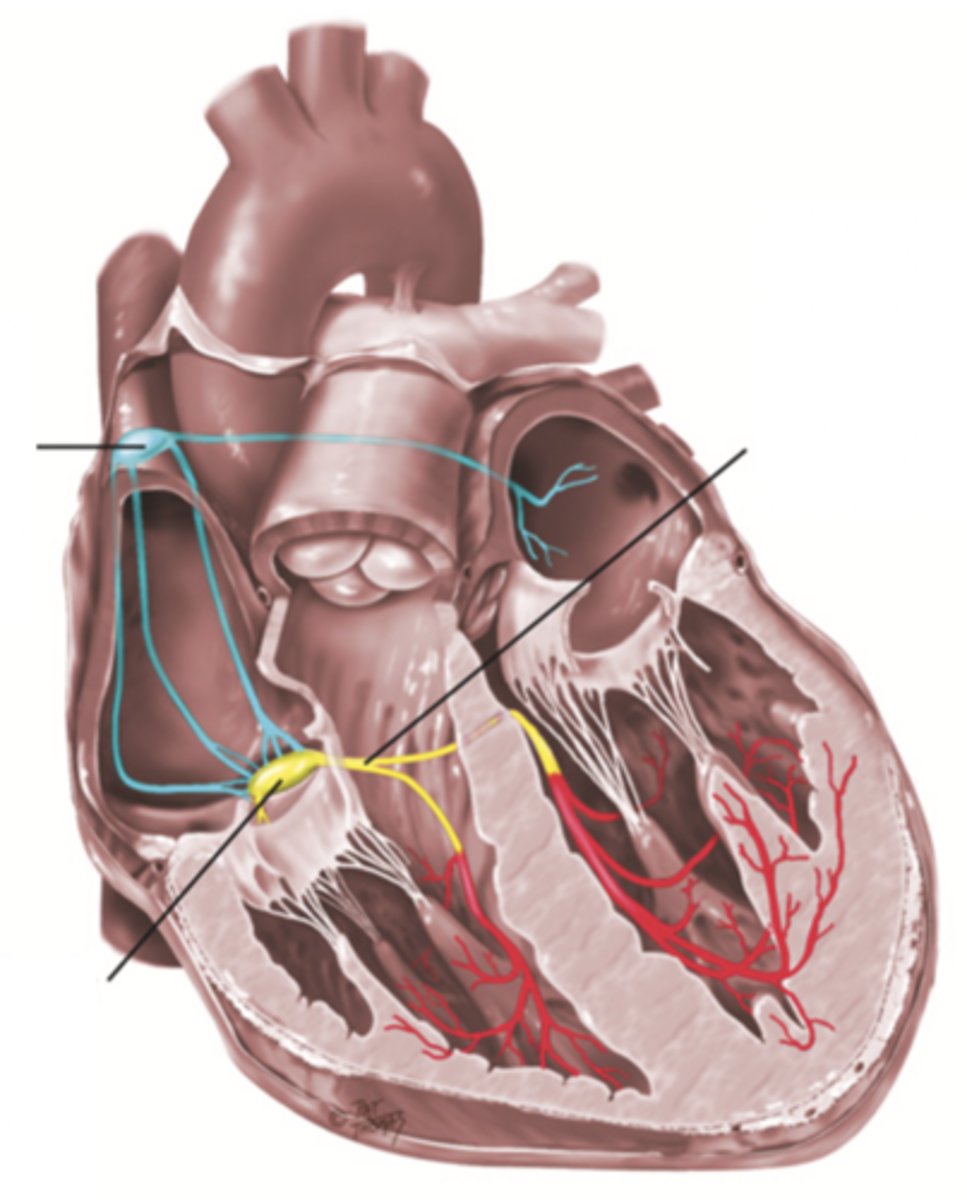

4 Parts of the Heart's Conduction System

- Sinoatrial (SA) node

- Atrioventricular (AV) node

- Bundle of His

- Purkinje fibers

Sinoatrial (SA) Node

Pacemaker of the heart conduction system, located at the right atrium (light blue)

Atrioventricular (AV) Node

The part that relays electrical impulses from atria into the bundle of his in the heart's conduction system; delayed slightly (yellow)

Bundle of His

Part of the heart's conduction system that transmits the cardiac impulse from the atrioventricular node to the purkinje fibers (red)

Purkinje Fibers

Fibers in the ventricles that transmit impulses to the right and left ventricles, causing them to contract